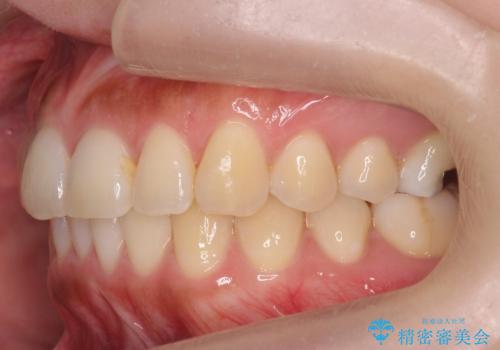

- 前歯のがたつきを主訴に来院。

前歯は目立つのでワイヤー矯正は絶対にしたくないとのことでした。

右上の奥歯を後ろに送り、前歯が出っ歯にならないように並べました。

また、右下の奥歯に一部目立たないように部分的なワイヤー矯正を行い、右下の奥歯が反対咬合になっていたのもしっかり中に入れて治療しています。

奥歯の反対咬合を治すのはインビザラインではかなり難しいのですが、しっかり治療できました。